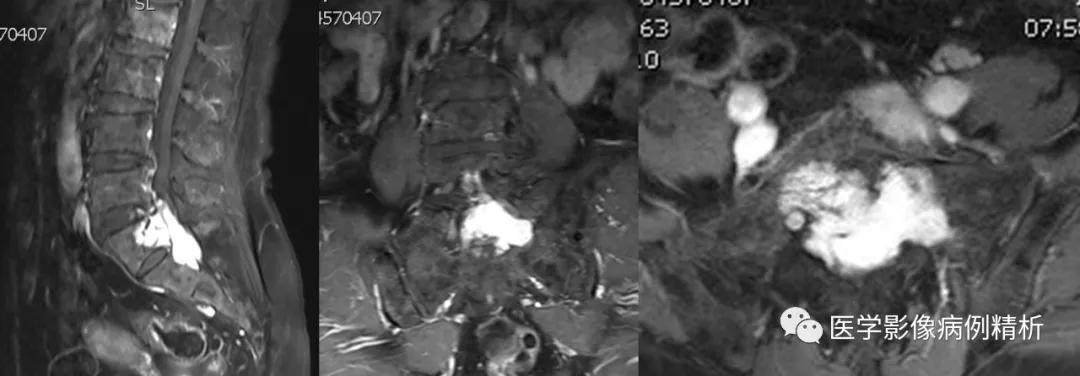

如图所示,红色箭头可见不规则形异常信号,轴位呈哑铃型,病灶前缘侵及骶1、2椎体后缘,绿色箭头见骨质局部破坏,病灶T1低信号,T2稍高信号,压脂像明显高信号,信号尚均匀,腰4-5、腰5骶1椎间盘向后方突出,硬膜囊受压,蓝色箭头可见腰4-5椎间盘后缘纤维化小点状T2高信号,提示纤维环后缘撕裂。本例骶1-2椎间盘形成,骶1椎体腰化不完全。

如图所示,分别为T1WI增强矢状位、冠状位、轴位,T1WI增强矢状位与T2WI压脂像非常相像,关注椎管内脑脊液信号,T1WI增强为低信号与T2WI压脂像高信号正好相反。红色箭头所示病灶明显强化,呈亮灯征感觉,清晰显示病灶范围,绿色箭头所示为病灶侵及骶1椎体后缘形成不规则形骨质破坏区。

红色箭头:病灶位于骶1-2椎体水平,轴位呈哑铃型,CT见骶1-2椎体后缘受侵、骨质破坏;MRI见病灶主体沿骶管及双侧骶孔生长,以左侧骶孔为著,T1低信号,T2稍高信号,压脂像高信号,接近脑脊液信号。

绿色箭头:骶1-2椎体后缘见信号向内部侵犯,边缘毛糙。

描述:腰椎生理曲度存在,序列规整。所见椎体骨质边缘变尖、T1WI及T2WI均呈不均高信号,压脂像均匀低信号。腰4-5、腰5骶1椎间盘向后方突出,硬膜囊受压。骶1-2椎体水平骶管及双侧骶孔扩大,内见哑铃型异常信号,大小约6cmx5cmx3.5cm,T1WI低信号,T2WI稍高信号,压脂像高信号,病灶侵及骶1-2椎体后缘骨质,增强明显强化。